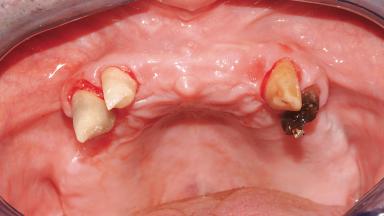

Immediate Loading of Six Implants in the Maxilla and Final Restoration with a Full-Arch Gold/Ceramic FDP Involving the Concept of Tilted Implants

A 61-year-old male patient with a failing fixed maxillary rehabilitation and a fixed mandibular rehabilitation requested a new fixed maxillary rehabilitation. The patient was wearing a temporary metal-reinforced maxillary bridge inserted two years before the consultation. He reported that his previous dentist did not want to insert a definitive framework because he considered the residual teeth to have a negative prognosis. The patient reported a history of recurrent caries and endodontic complications as the main reason for the previous extractions. The anamnesis was negative for periodontal disease and bruxism. The patient’s chief compliant was the mobility of his maxillary prosthesis, which needed to be re-cemented frequently, and discomfort during chewing.Moreover, the patient was not satisfied with the esthetic appearance of his maxillary teeth, which he found too long. The patient asked for a stable and comfortable fixed maxillary rehabilitation and firmly rejected any removable solution.

Defining Characteristics Fully edentulous upper jaw to be rehabilitated with four or more implants

Bone Volume Deficient horizontally, allowing simultaneous augumentation